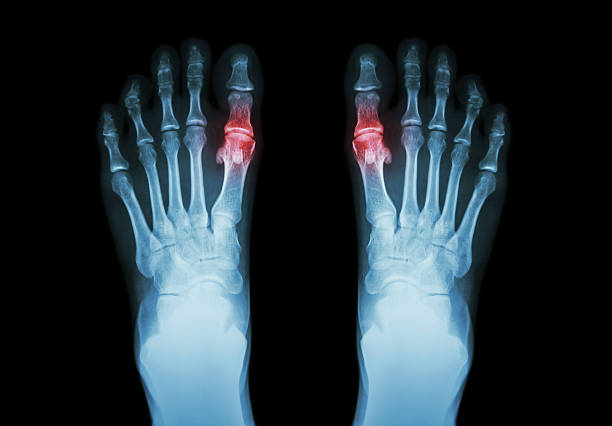

요산이 쌓이고 관절에 요산 결정체가 만들어지며 '통풍 관절염'이 발생합니다.

엄지발가락 뿌리나 발등, 발목 등이 붓고 극심한 통증이 생기며 붉은 발적(급성 염증 시 혈관 충혈에 의해 피부가 빨간빛을 띠는 것)이 생기고 걷기 힘들 정도의 통증이 오게 됩니다.

낮보다는 밤에 통증이 심해지는 경우가 많으며 뼈마디가 울퉁불퉁 부을 수 있습니다.